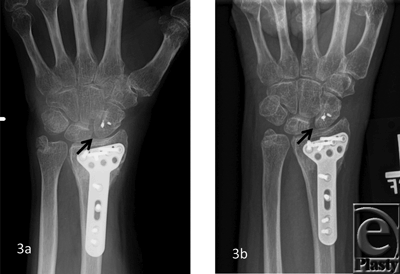

The patient demographics, clinical findings, X-ray, and 4D CT imaging findings as well as final patient disposition are depicted in Table 1. All subjects were successfully scanned in various wrist motions (Patient 1-4 videos). 4D CT image quality was adequate in all subjects, and carpal kinematic behavior was easily assessed in various wrist motions both before and after surgical repair. The normal postoperative (Patient 1-3 videos) and altered carpal kinematic behaviors (Patient 4 videos) correlated well with the clinical findings. In the operated wrists (Figs 2-4), while X-rays demonstrated slight gaping after scapholunate ligament repair, kinematic imaging demonstrated no abnormal widening with dynamic motion and showed normal dorsally hinged scissoring type scapholunate motion with motion. However, normal mid-carpal initiated wrist motion on flexion/extension was replaced by radiocarpal initiated motion, likely because of midcarpal stiffness/scarring. Clinical suspicion of ulnocarpal abutment was also confirmed in both wrists of Patient 4 (Fig 5).

Patients with obvious findings necessitating surgical intervention such as the radiographic findings already mentioned, or more complex injuries such as a perilunate or lunate dislocation, may have questionable radiographic findings even after surgical repair/reconstruction. A persistent 3- to 4-mm scapholunate gap suggesting persistent ligamentous instability despite repair on multiple unchanging postoperative X-rays following fixation removal can be common finding that delays initiation of wrist motion rehabilitation and return to normal function, as it was observed in patients 1 to 3. For these reasons, we have begun incorporating Dynamic 4D CT imaging into our postoperative imaging following commencement of wrist motion and rehabilitation for patients with interosseus ligament injuries of the wrist. We could obtain good diagnostic quality imaging and 4D reconstructions in all subjects without significant beam hardening artifacts similar to earlier results on 256-row detector study.34 For this modality to have its highest diagnostic sensitivity and specificity, it requires a thorough knowledge of wrist kinetics to appropriately appreciate what motion is normal and what motion is abnormal. This requires collaboration of hand surgeons and radiologists with study of normal dynamic studies and comparison with abnormal studies. These cases represent our early experience with this modality and how it has assisted in appreciating the postinjury wrist motion as well as helped guide activity and treatment postoperatively.